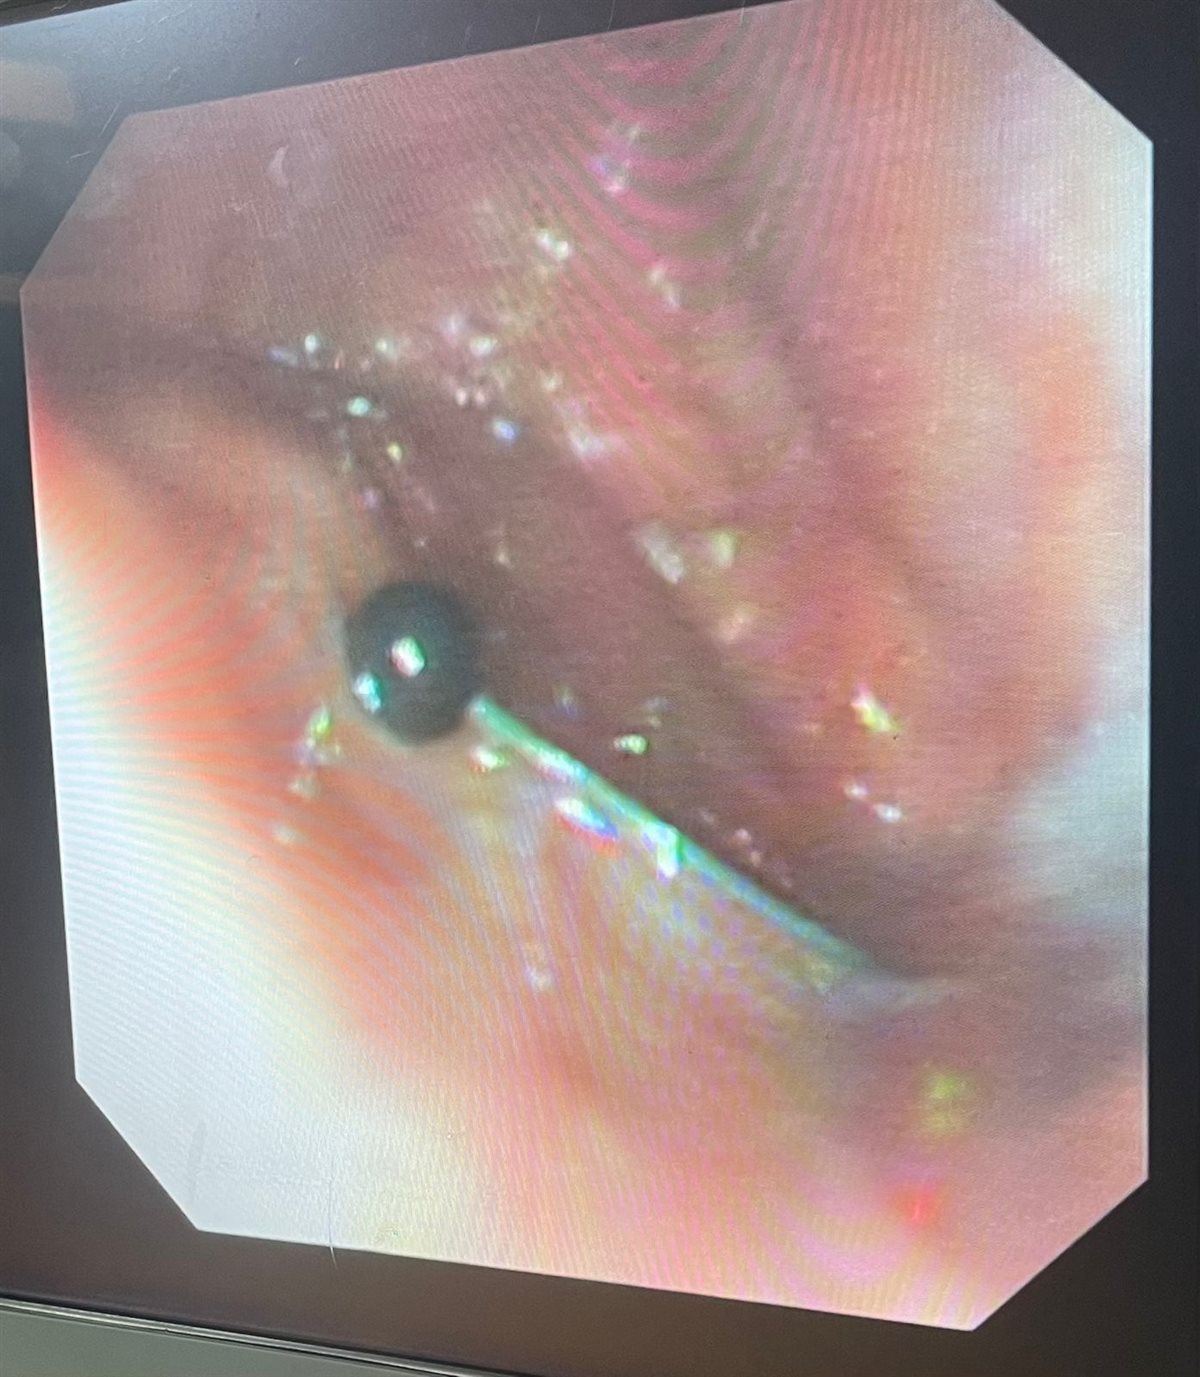

نجح فريق طبي من وحدة أمراض الجهاز الهضمي والكبد ومناظير الأطفال بقسم طب الأطفال بمستشفى سوهاج الجامعي في إجراء تدخل دقيق لاستخراج دبوس من معدة طفل يبلغ من العمر أربع سنوات، باستخدام منظار معدة خاص بالأطفال، دون حدوث أي مضاعفات، وقد غادر الطفل المستشفى بعد ثلاث ساعات فقط من الإجراء، وهو في حالة صحية جيدة.

وأكد الدكتور أحمد كمال، المدير التنفيذي للمستشفيات الجامعية، أن التعامل مع الحالة تم بسرعة وكفاءة، حيث تمكن الفريق الطبي من استخدام المنظار الخاص بالأطفال لاستخراج الدبوس دون أي تدخل جراحي، مما ساهم في خروج الطفل من المستشفى في نفس اليوم بحالة ممتازة.